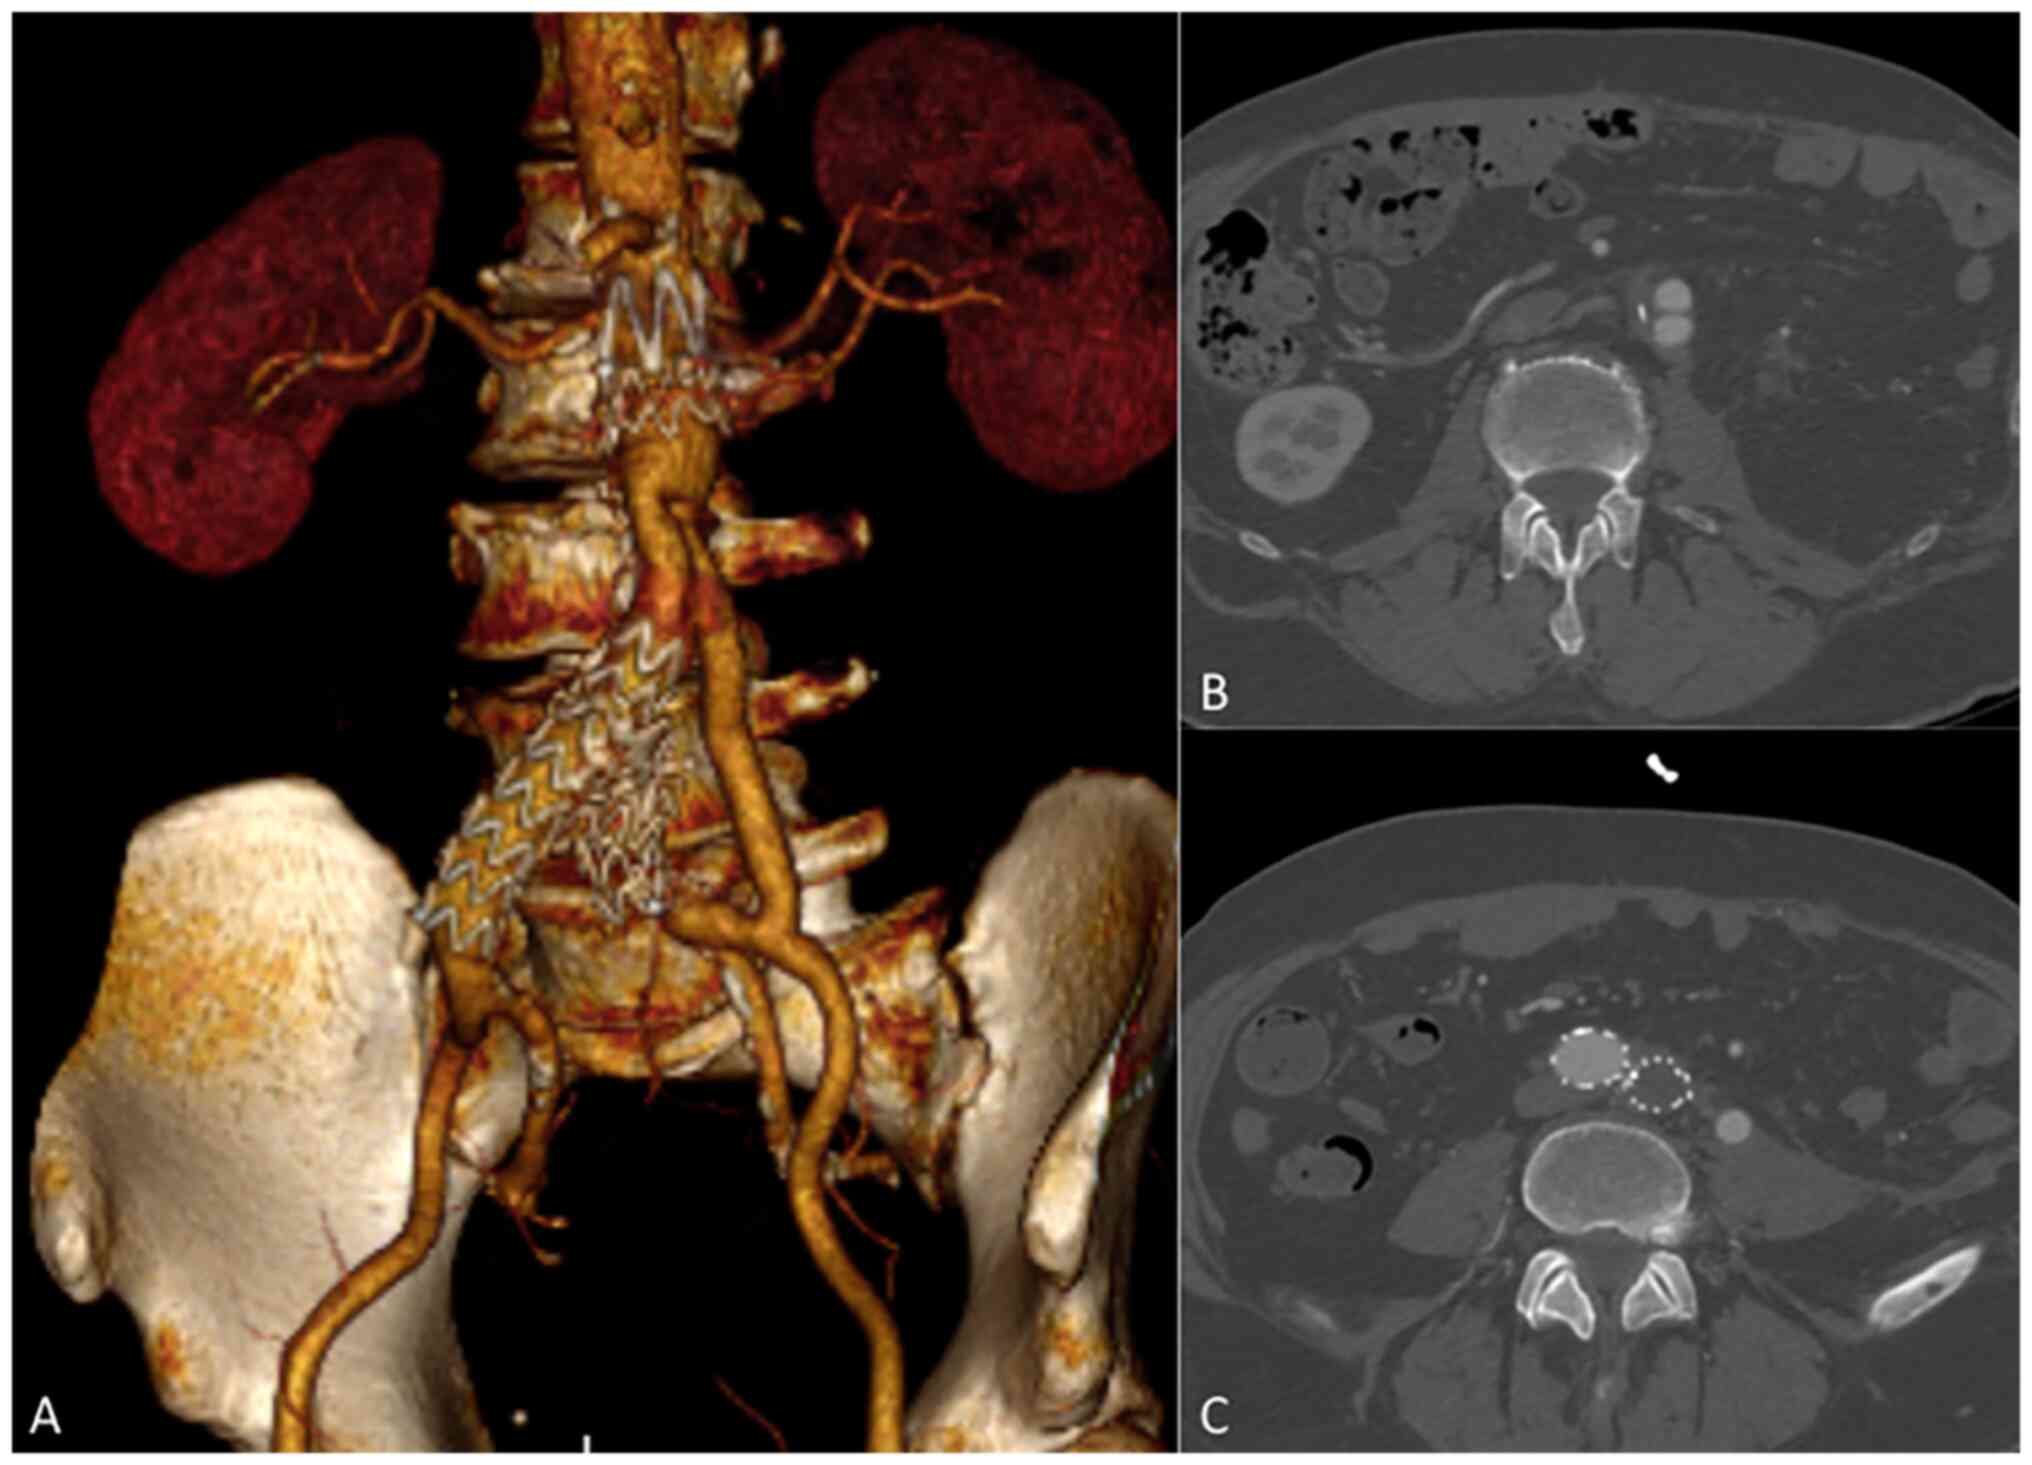

After 1 week, the abdominal and pleural drainages were removed and, 1 week later, the patient could resume feeding on a soft diet, without any signs of bleeding. A control CTA revealed both a significant reduction in pleural and abdominal effusions and patency of the bifurcated Silver Dacron graft (Fig. 3A-C); therefore, the intravenous antibiotic therapy was discontinued, and treatment with oral clarithromycin (500 mg every 12 h) was started. After a further week, the patient was transferred to a Rehabilitation Centre, where he followed a plan of re-education with a continuance of oral antibiotic therapy for 3 months in accordance with his clinical conditions and the laboratory tests. After 3 months, the patient was discharged from the Rehabilitation Centre and after 9 months of follow-up, the patient was in good clinical condition without signs or symptoms of reinfection.

Figure 3

(A-C) Three-dimensional reconstruction of postoperative computed tomographic angiography underlying the aorto-bi-iliac reconstruction after the partial explantation of the stent-graft.